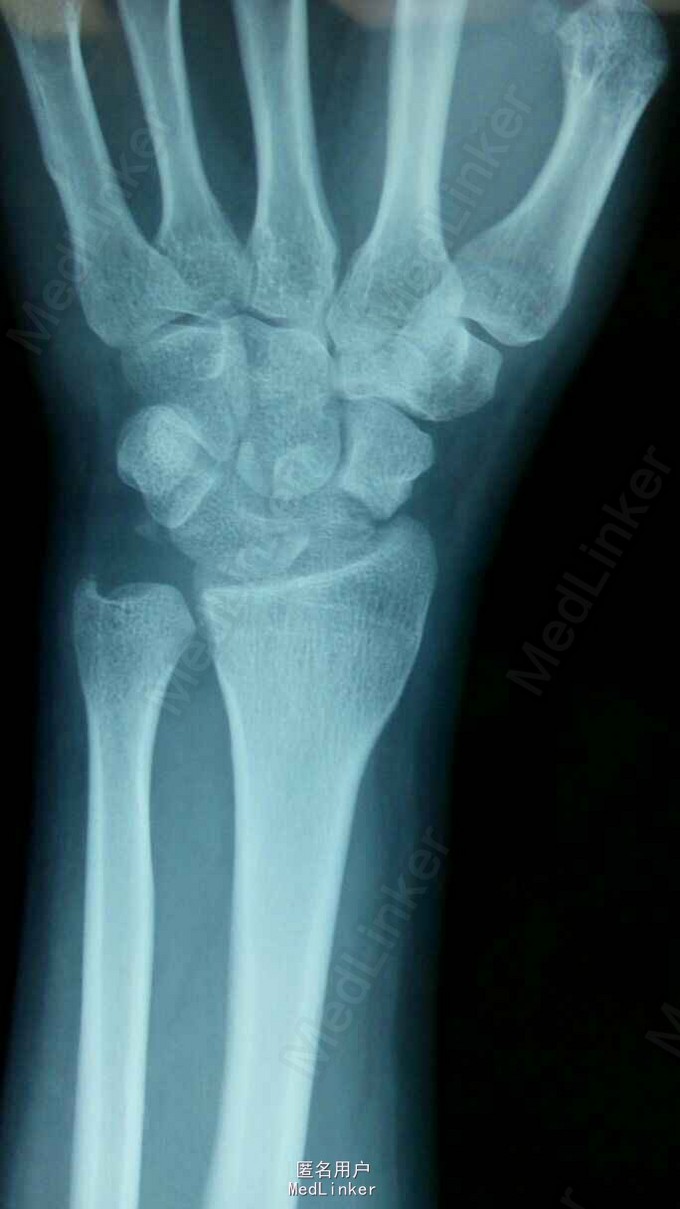

经舟骨月骨周围脱位

患者1天前骑摩托车摔伤致左腕部肿痛不适,活动受限,桡侧三个半手指麻木不适

腕关节肿胀明显,桡侧三个半手指感觉迟钝,腕关节住被动活动受限

经舟骨月骨周围脱位,闭合复位失败后,行手术治疗,月骨切开复位,舟骨空心钉固定

术后外固定架限制腕关节活动,一般6周后去除外固定架,适量活动锻炼腕关节,舟骨骨折定期复查拍片